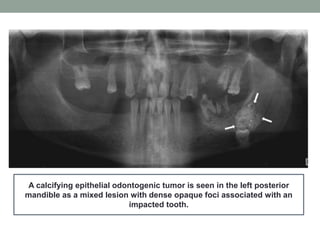

A calcifying epithelial odontogenic tumor is seen in the left posterior

mandible as a mixed lesion with dense opaque foci associated with an

impacted tooth.

A calcifying epithelialodontogenic tumor is seen in the left posterior mandible as a mixed lesion with dense opaque foci associated with an impacted tooth.